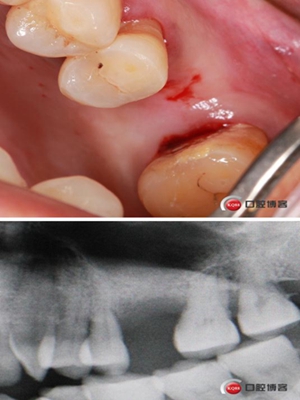

患者女性,58歲,身體健康,無不良咀嚼習慣,不吸煙、不飲酒。兩年前因左上后牙反復咬合痛,嚴重影響進食就診,檢查發(fā)現(xiàn)26號牙根尖周炎癥明顯,周圍骨吸收嚴重。拔除患牙,徹底掻刮,由于骨缺損嚴重,沒能即刻種植。6個月后來門診種植。

骨高度僅有3mm,寬度充足。計劃外提升,根據(jù)骨質(zhì)情況決定是否同期植入植體,切開翻瓣,暴露上頜竇頰側(cè)骨壁。